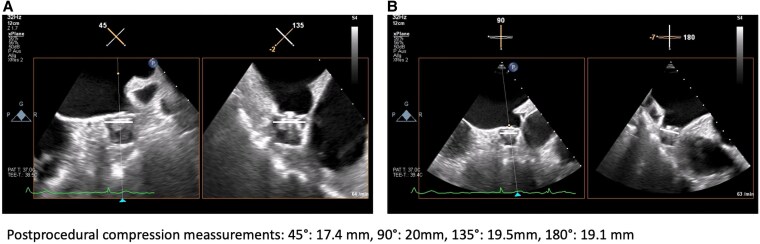

Case summary: In an 82-year-old male patient with symptomatic persistent AF, CHA2DS2-VA Score of 4 and HASBLED Score of 3 due to previous gastrointestinal bleeding were scheduled for a concomitant PVI + LAAC procedure. For minimum risk, a streamlined approach utilizing a single femoral vein puncture in combination with a suture-based closure system (Perclose Prostyle, Abbott) was performed. The transoesophageal echocardiography (TOE) LAA landing zone measurements were achieved directly prior ablation. Pulmonary vein isolation was performed with pentaspline PFA catheter (FARAPULSE). Although a swelling of the left atrial ridge was observed, a 24 mm WATCHMAN FLX device was successfully implanted. The patient was mobilized after 2 h and discharged on the next day. After 2 months on OAC, TOE found no gaps or leakage of the LAAC device and OAC was switched to acetylsalicylic acid monotherapy.

Discussion: A streamlined concomitant PFA-based PVI and LAAC procedure utilizing FARAPULSE and WATCHMAN FLX devices seems to be feasible and safe. Swelling of the ridge after PVI was observed; however, the sizing measurements have been performed prior PVI, and the LAAC procedure was successful with no evidence for gaps or leakage. A concomitant approach might be a suitable option for selected patients.